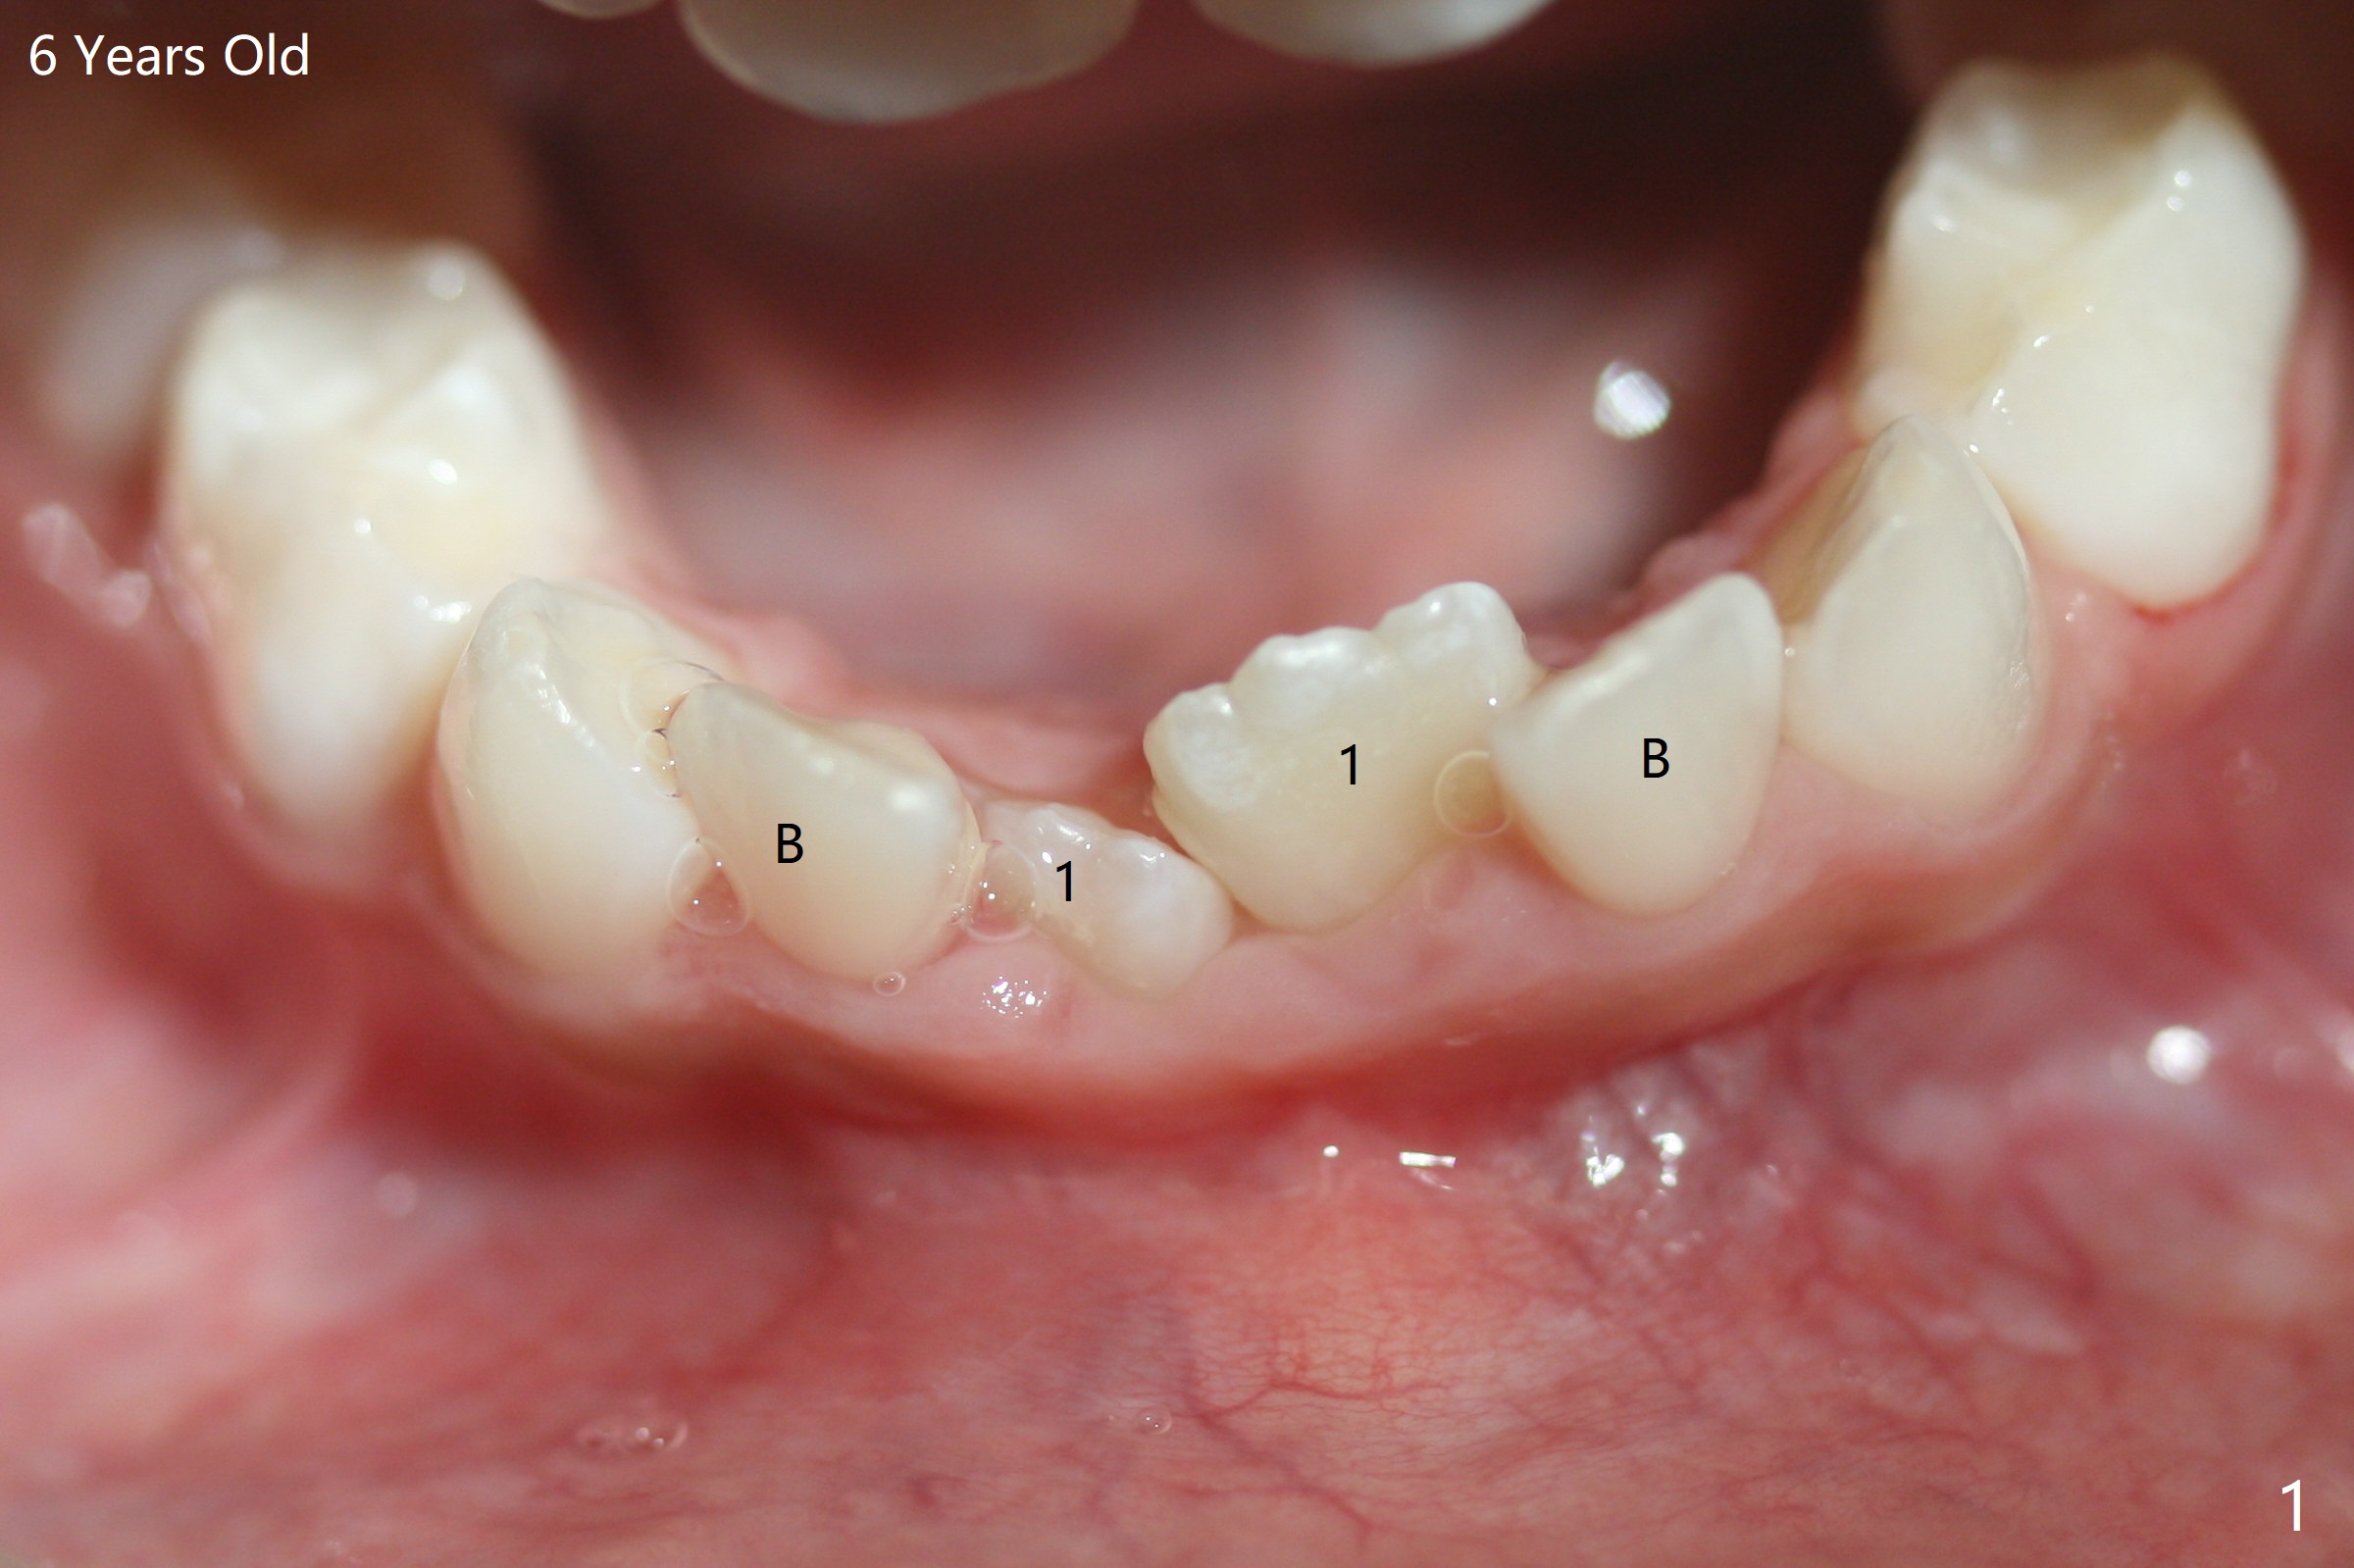

一位女孩具有家族性牙齿拥挤史,6岁下中切牙刚萌出时就显示拥挤(图一),九,十一岁相当明显(图二,三),十一岁正好处于新冠病毒流行期间,妈妈同意拔除四个第一双尖牙,让牙列自行调整一年左右。初步检查表明上下磨牙近远中位置正常。不紧不慢使用弓丝排列牙弓,让7充分萌出。牵引上尖牙时,注意磨牙位置改变,最好同时使用下6(二类牵引)以及上5-7作为支抗。